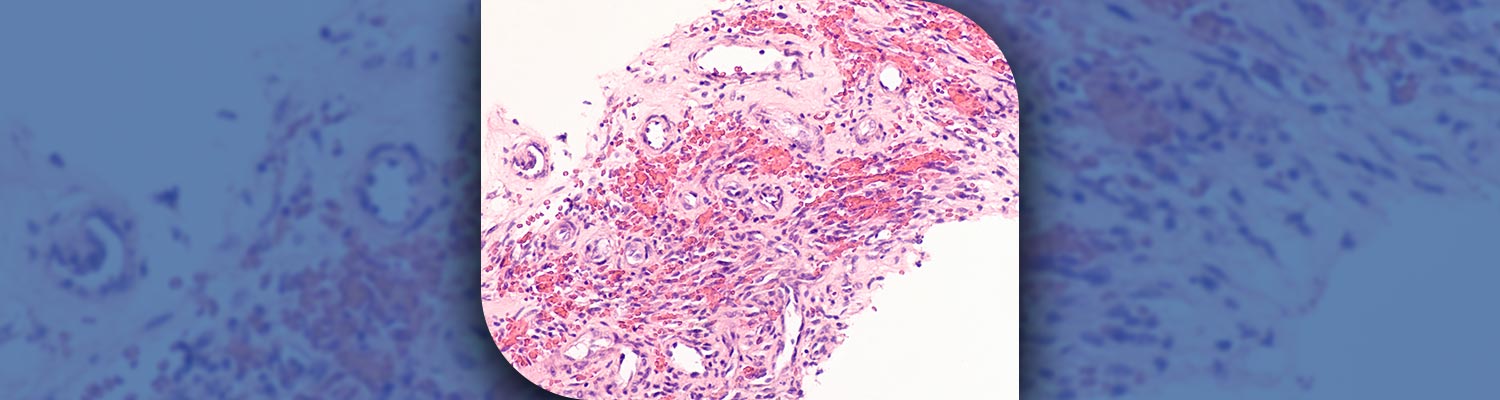

Content Kaposi sarcoma News & Events News & Events News Four in ten cancer cases could be prevented globally Read More 03.02.2026 20.08.2025 Global burden of cancer attributable to HIV: a worldwide incidence analysis SEE MORE News & Events Press Releases Press Releases Press Release Four in ten cancer cases could be prevented globally Go to PDF 03.02.2026 23.10.2015 HIV-positive people disproportionately affected by infection-related cancers SEE MORE Press Releases Highlights Highlights Featured News World Cancer Day 2026 - Four in ten cancer cases could be prevented globally Read More 04.02.2026 SEE MORE Highlights Research Project Websites Research Project Websites Global Cancer Observatory